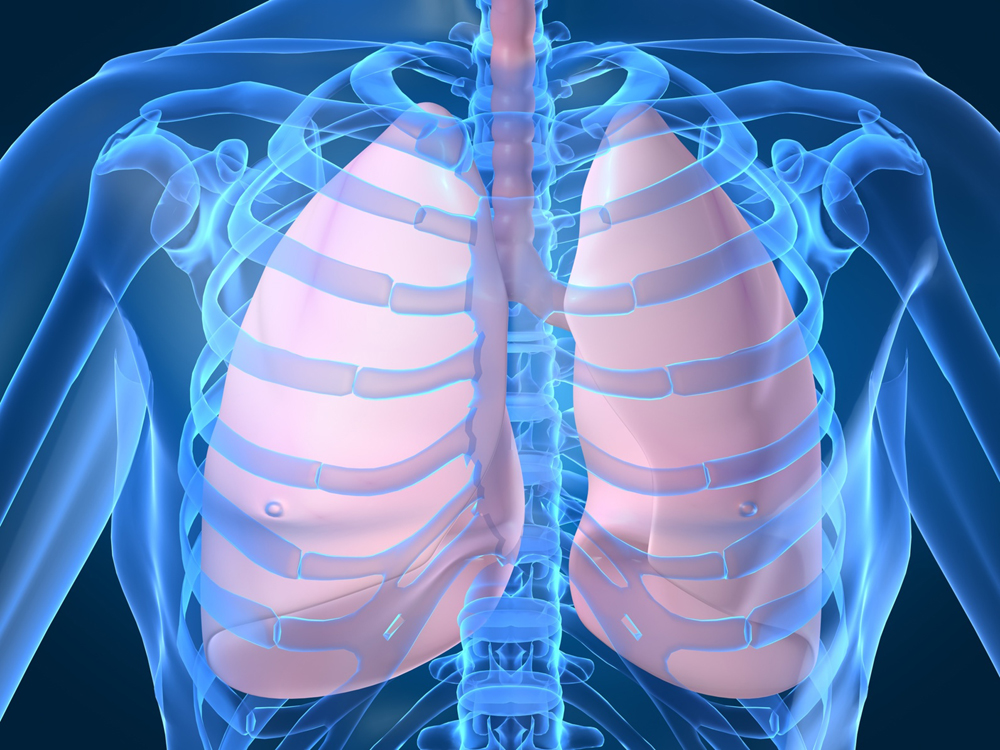

Анатомия межплеврального пространства

Раздел: Фотоэссе